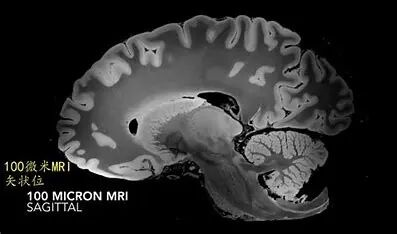

MRI即磁共振成像,其工作原理基于核磁共振现象,特别是氢原子核(质子)在强磁场中的行为。当人体置于强大的静磁场中时,体内的氢原子核会对齐。通过向这些原子核发射特定频率的无线电波脉冲,可以使它们偏离平衡状态,进而在恢复平衡时释放能量,这些能量被专门的接收线圈探测并转化为电磁信号。通过对这些信号的收集和解析,可以重建出人体内部的详细图像。

MRI不涉及电离辐射,因此对患者相对安全,尤其适合频繁成像的患者群体。MRI能够提供高分辨率的软组织图像,广泛应用于神经系统、肌肉骨骼系统、心血管系统以及腹部和盆腔器官的诊断和研究。

MRI 尤其擅长

软组织成像